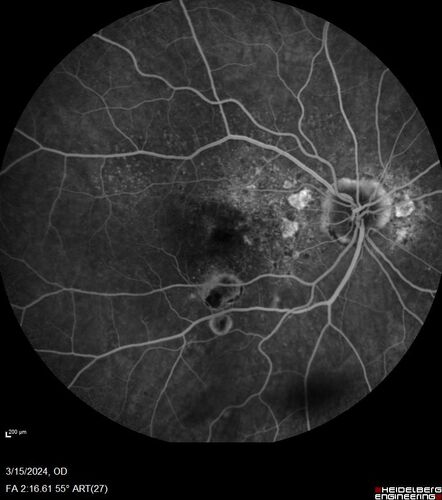

Fresh BRAO in patient with wet AMD

91 year old female She noticed last night a shadow over the left eye. When she closes her right eye she cannot see the bottom of the vision in the left eye. This is new.

VA OD: sc20/32-1

VA OS: sc20/32-2

BRAO in patient under treatment for wet AMD